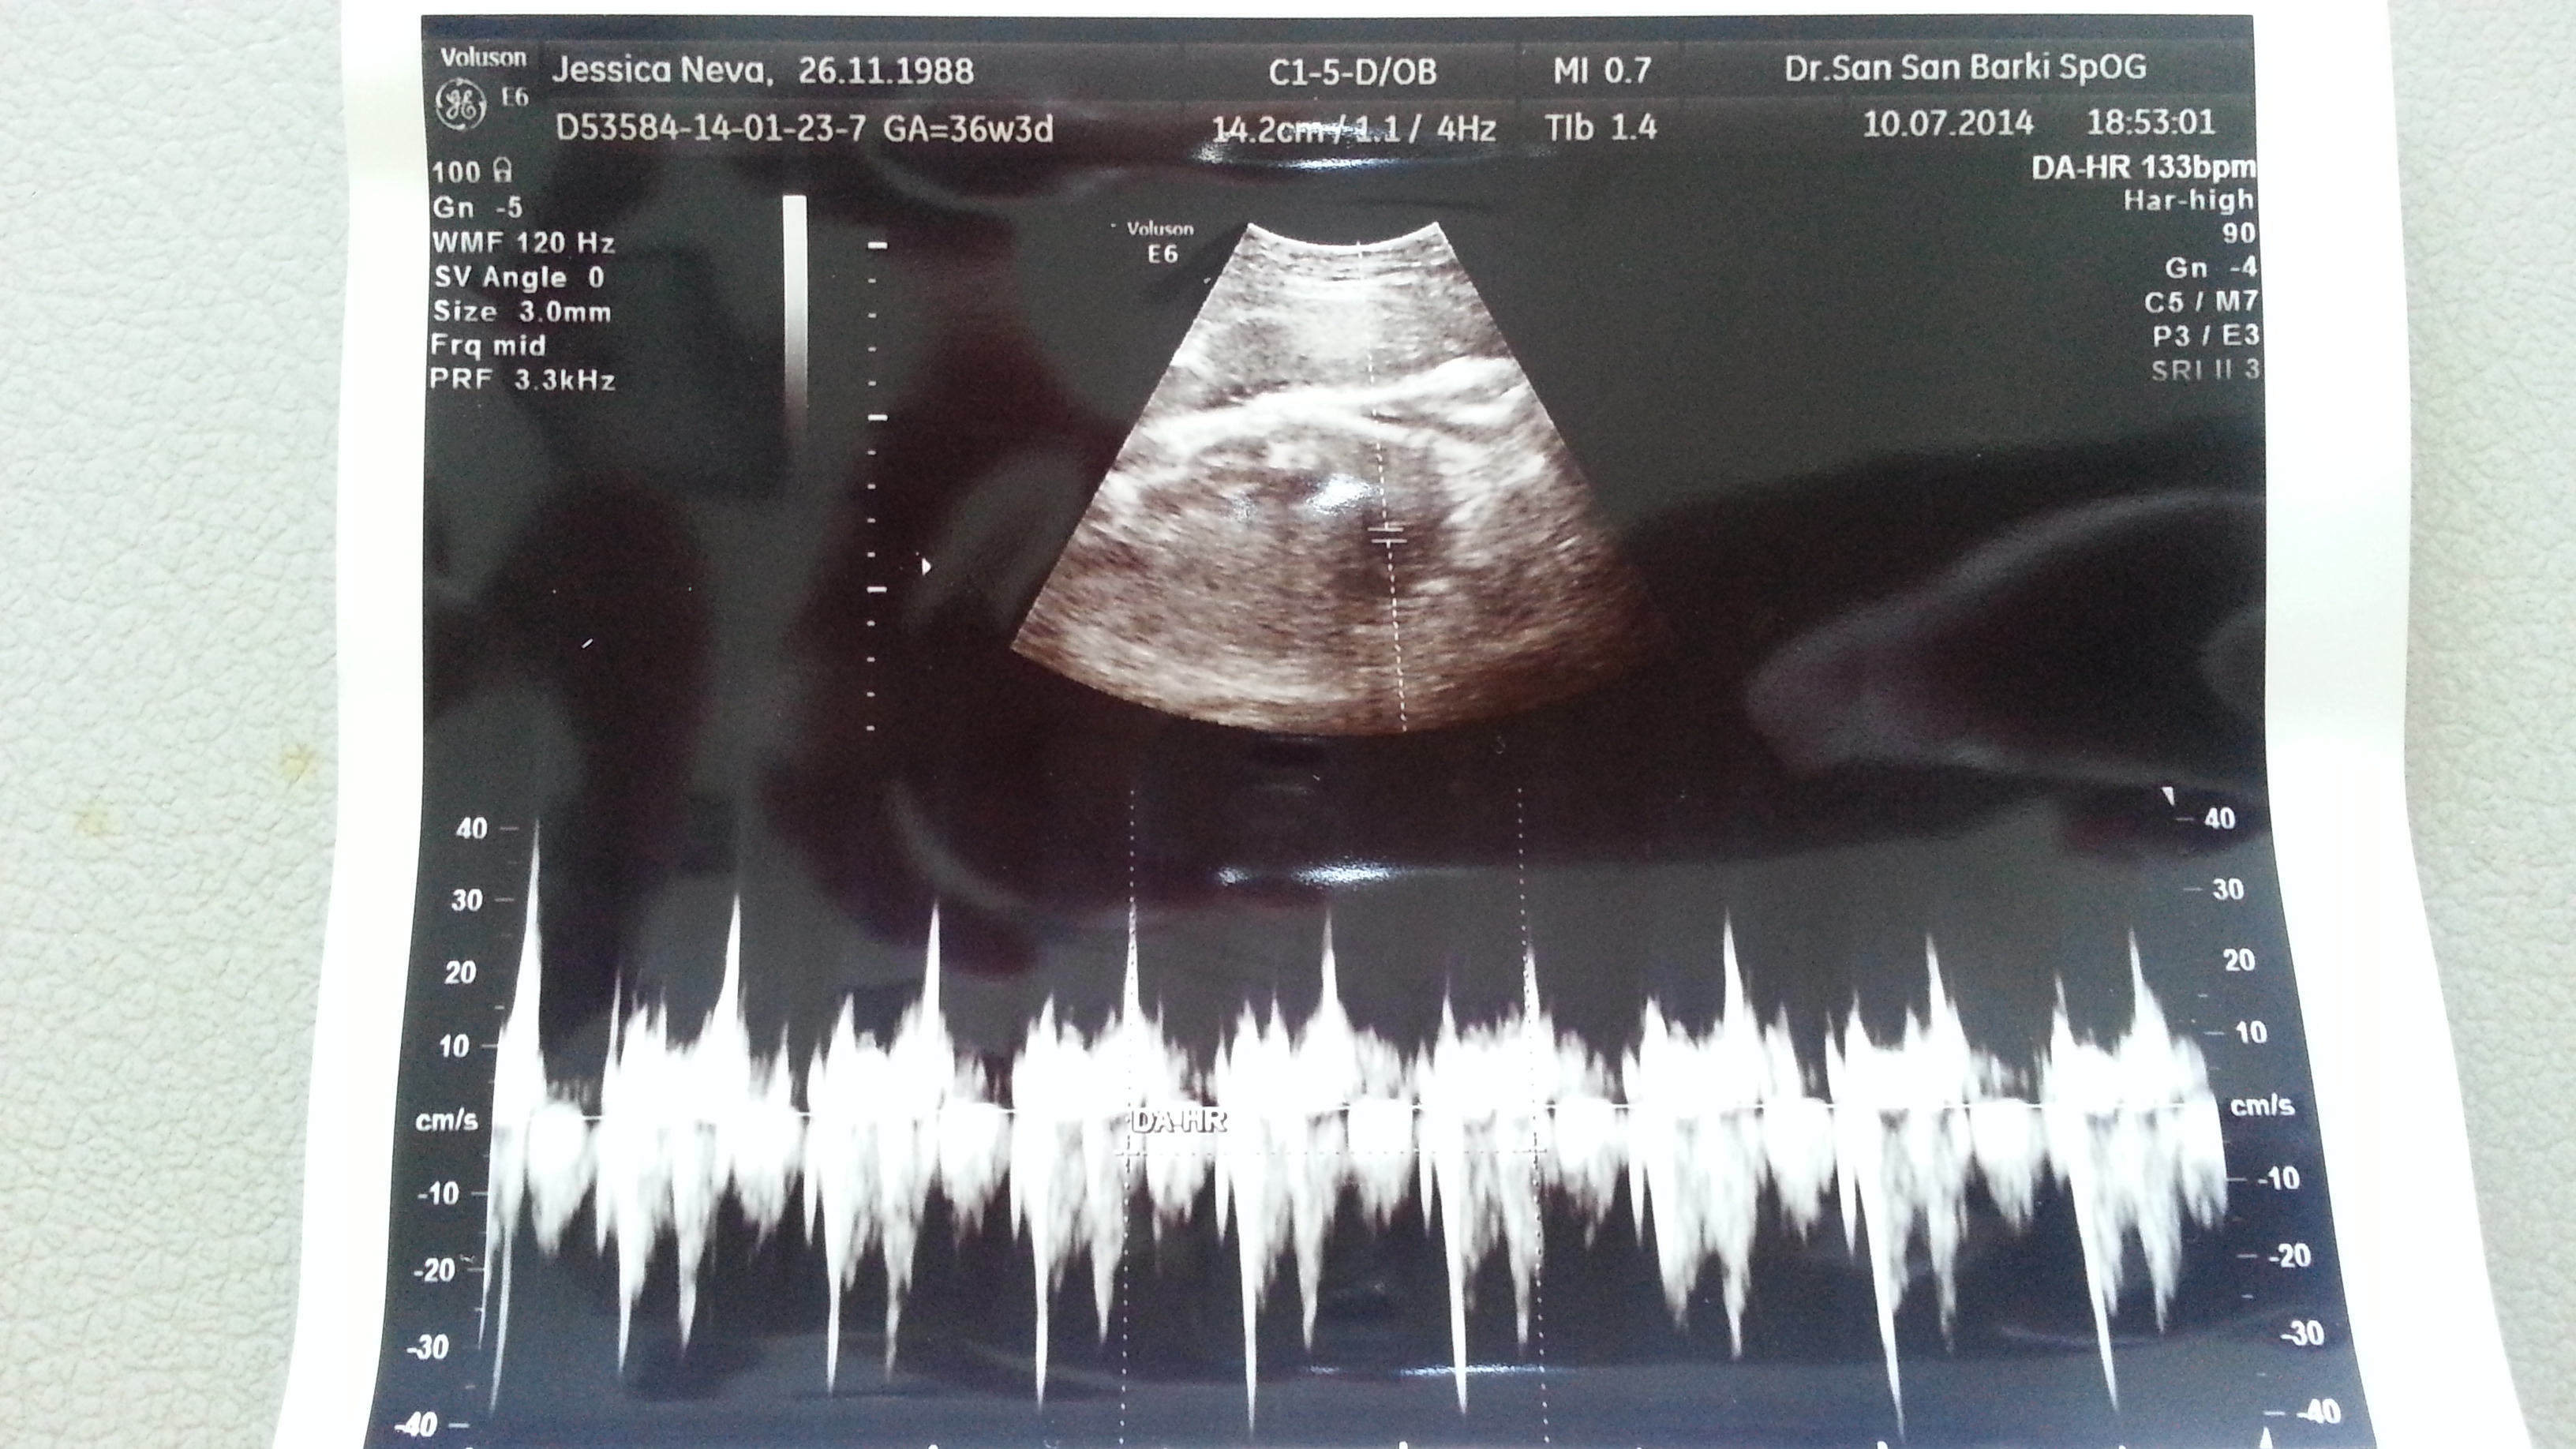

From this week onwards, we will visit our obgyn on a weekly basis. On week 36, the baby’s 2,6 kg and our obgyn’s happy as he wishes the baby to reach 3 kg before labour. His statement surprised us a bit because he never mentioned anything to us before. I just wonder how many more kilograms I will gain until labour as I’ve gained 13 kg up to today!